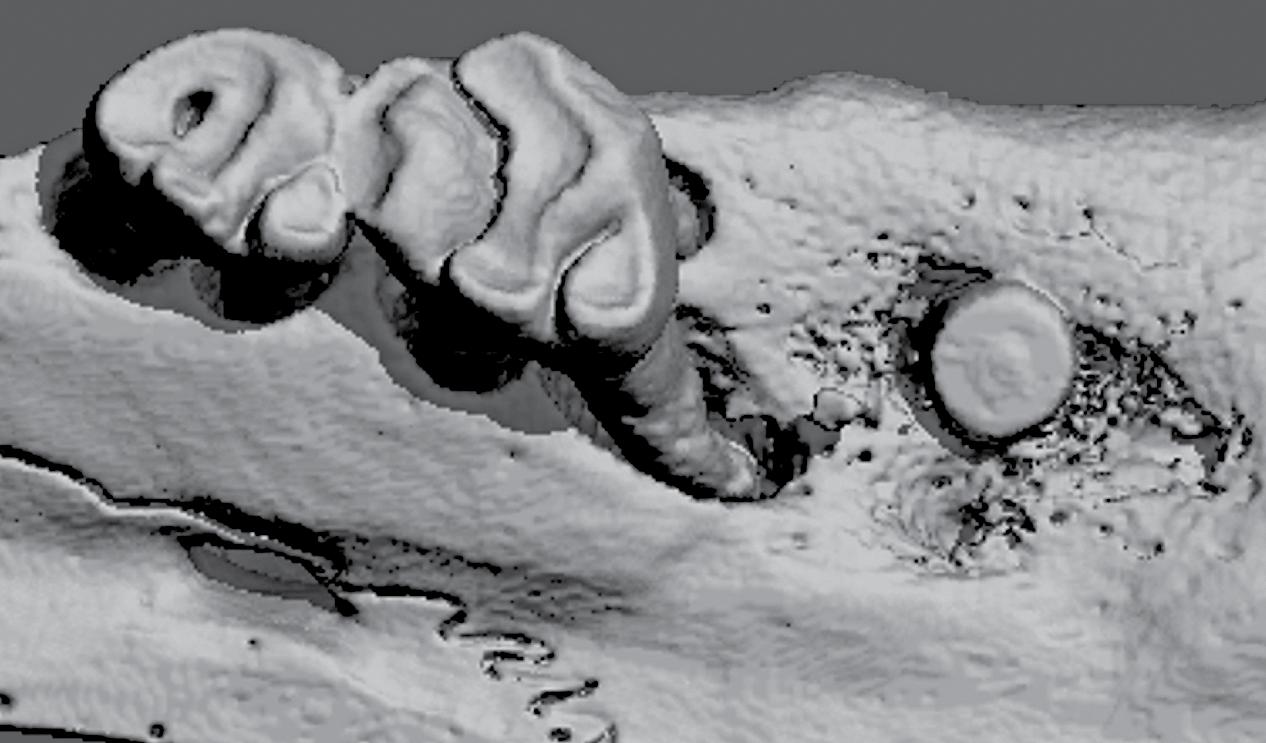

ITP Support – The ITP program has supported various aspects of this project, including: Regulatory; Pre-Clinical Animal studies; and Micro-CT, Histology and Statistical Cores. Ongoing guidance on how best to bring our product to the market has been provided by the Market Assessment and IP/ Commercialization Cores.

Competitive Advantage – As compared to conventional permanent, nondegradable cement-based products, RegendoGEL is biodegradable, and stimulates its replacement by regenerated natural dental pulp and dentin tissues. In vivo animal studies showed that RegendoGEL can regenerate dentin ~5x faster than existing products on the market. RegendoGEL’s biocompatible, non-inflammatory and biodegradable properties reverse the degenerative spiral of tooth decay, which normally progresses from a small cavity and filling to larger fillings, eventually leading to endodontic treatment and tooth replacement therapies.

Image credits from our ITP teams: S. Feinberg, L. Bertassoni, P. Yelick, Oraxsys Therapeutics, W. Giannobile, J. Taboas